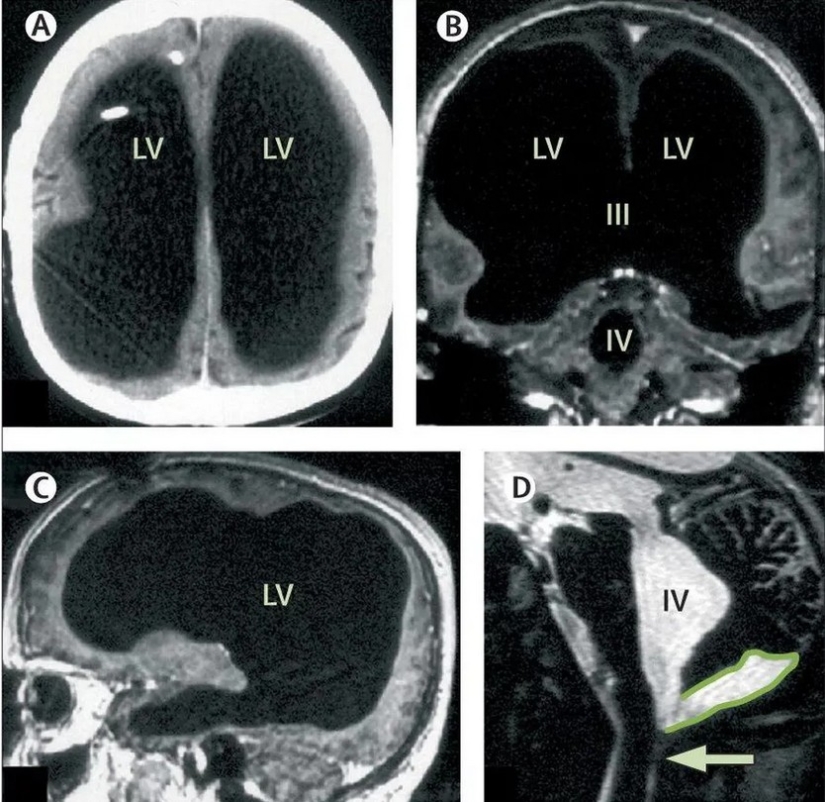

Las piernas doloridas se olvidaron de inmediato, ya que de repente resultó que el paciente estaba literalmente "vacío en la cabeza". Una resonancia magnética mostró que el cráneo de Mathieu estaba casi completamente lleno de líquido. Sólo quedaba una fina capa del cerebro. De acuerdo con todas las leyes de la naturaleza, tal persona no podría vivir, y mucho menos trabajar en una institución estatal, criar hijos y conducir un automóvil. El hombre fenomenal tenía un coeficiente intelectual de 75, que no es mucho, pero dentro del rango normal.

El paciente nunca se quejó de problemas en la cabeza. Lo más probable es que si no fuera por el dolor en las piernas, Mathieu habría vivido toda su vida sin saber qué persona única es. Los especialistas se comprometieron a estudiar al francés y encontraron la causa de su enfermedad. Su cerebro se fue deteriorando lentamente a lo largo de 30 años, y el líquido ocupó su lugar. Este proceso se llama hidrocefalia o hidropesía del cerebro.

Mathieu contrajo hidrocefalia en la primera infancia. Hasta los 14 años, caminó con una derivación especial en el cráneo a través de la cual se podía drenar el líquido. Luego se retiró el dispositivo, ya que se consideró que el chico había crecido y se había recuperado. Y, de hecho, la enfermedad comenzó a pasar en secreto. El líquido se acumuló en el cráneo y el cerebro colapsó gradualmente. Pero durante 30 años esto no afectó el bienestar del hombre. Los médicos se encogen de hombros porque no saben cómo ayudar a Mathieu y si necesita ayuda. Por ahora, solo continúan librándolo del líquido que se acumula en su cabeza.